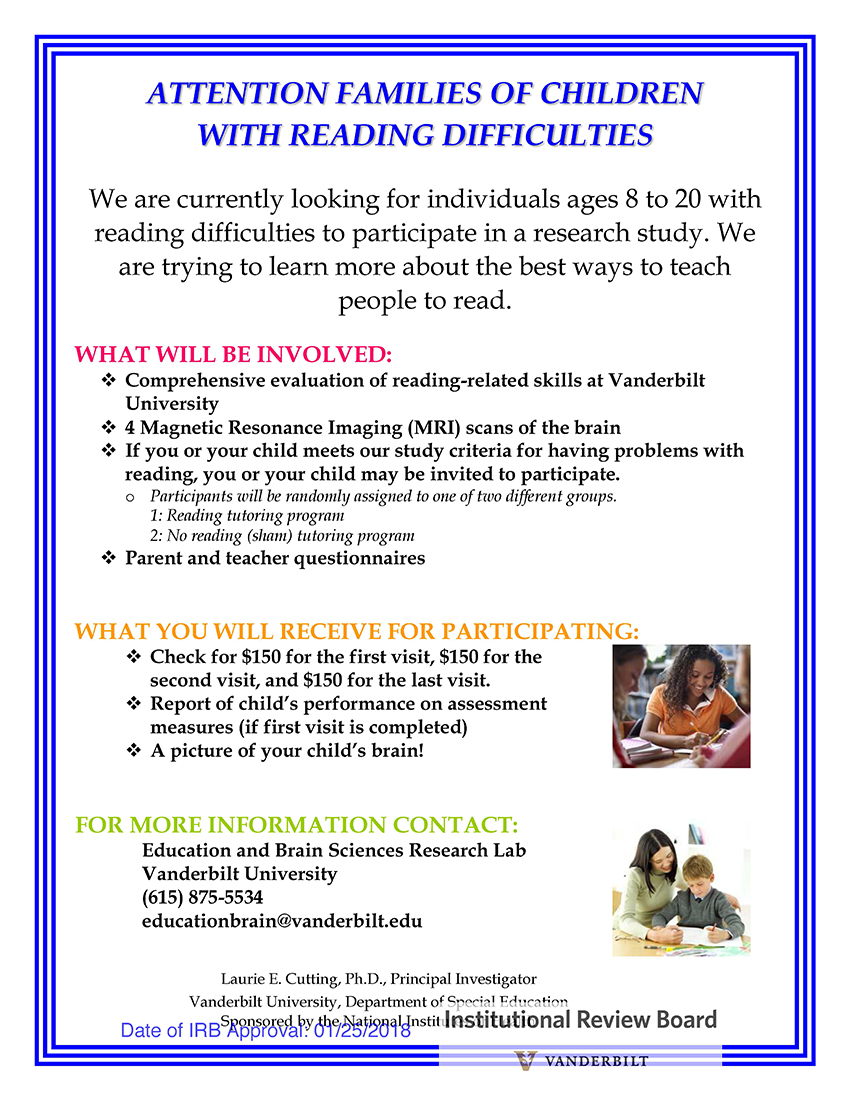

- Individuals age 8–20 with reading difficulties but no diagnosis of NF1

Study recruitment will be ongoing for the next three and a half to four years, providing funding continues. The study, which will last about 26 weeks, involves an initial phone screening to determine eligibility, lab visits at Vanderbilt, intensive reading interventions, MRI scans and, for some participants, an investigational study medication. Participants will be compensated up to $1,050, in addition to travel reimbursement for families living outside Middle Tennessee.

The goal of the study is to determine the best ways in which people with neurofibromatosis Type 1 who struggle with reading can learn to become good readers. The principal investigator of the study is Laurie Cutting, Patricia and Rodes Hart Professor of Special Education at Peabody College, professor of pediatrics in the Vanderbilt School of Medicine, and associate director of the Vanderbilt Kennedy Center.

Please see the two flyers below for more detailed information about the study.